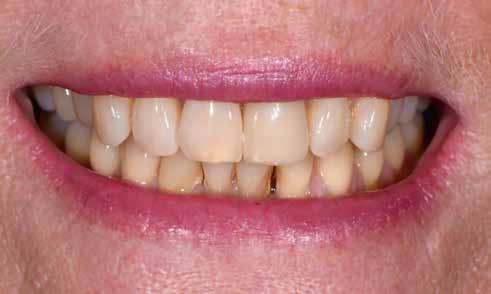

KIRÁLYKATEGÓRIA –FRONTFOG-MEGOLDÁS

Implantátum-protetikai ellátás digitális tervezéssel

Egyetlen frontfog pótlása most is – akárcsak korábban – a királykategóriába tartozik. Bármely kis formai vagy színhiba kíméletlenül megmutatkozik minden mosolynál. Ezzel hihetetlen szintet nő, vagy csökken a páciens életminősége. Stefanie Flentje esetbemutatása ismerteti, hogyan valósíthatunk meg sikerrel implantátum elhorgonyzású borítókoronát a frontterületen.

A 64 éves hölgypáciens esztétikus pótlást kívánt 21-es foga helyén, amelyet balesetet követően 2022-ben távolítottak el. Az összes foga egészséges és vitális volt, így a 21-es régióba implantátum került, amelyre cirkónium-dioxid koronát terveztünk. Az implantátum típusát, pozícióját, átmérőjét egyedi anatómiai adottságainak és az adott helyviszonyoknak megfelelően választottuk meg.

Pácienseset

33 éves páciens konzultált a rendelőben 3 évig tartó fogszabályozása elemeinek eltávolításáról szájából. A kárieszek eltüntetésén kívül optimalizálni szerette volna esztétikai kinézetét. Az első esztétikai elemzés a frontfogak kedvezőtlen hossz-szélesség arányát mutatta (1. kép). A bal felső szemfogat a pulpa elhalása következtében endodonciai kezelésnek is alá kellett vetni.